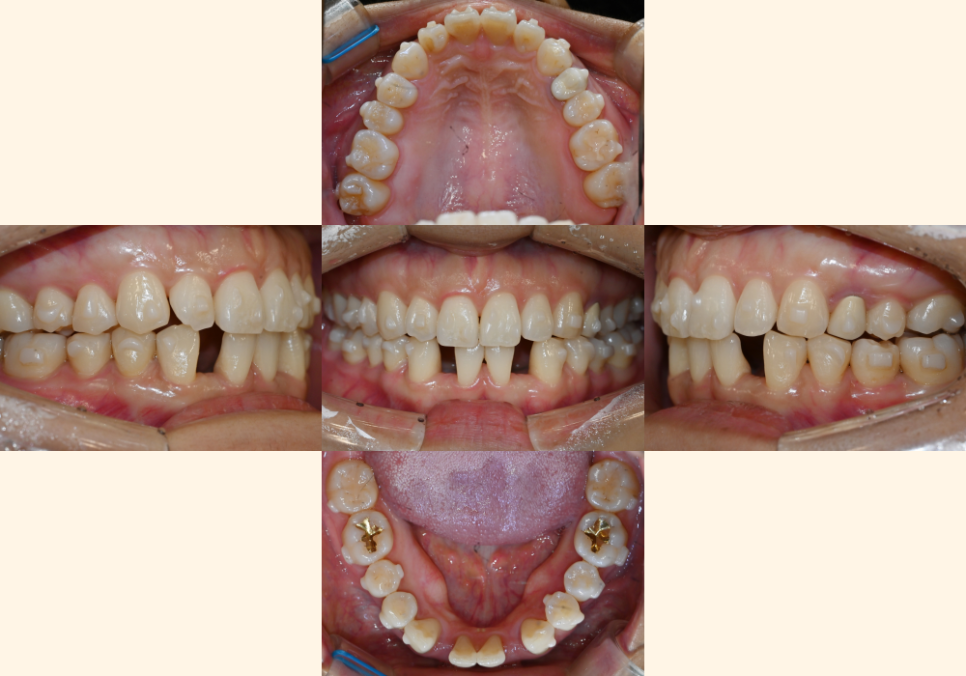

| 4. 단계별 치료 과정

첫 번째 단계

24.03.07

치료는 인비절라인 투명 교정 장치 제작 후

단계별로 장착합니다.

기울어지고 벌어진 치아들을

점진적으로 올바른 위치로

이동시키는 과정입니다.

24.08.12

초기에는

주로 치아들 사이의 공간을 정리하고,

과도하게 깊게 물리는 부분을

해소하는 데 집중하게 됩니다

25.02.10

교정 장치는

2주마다 새로운 단계로 교체 하면서

치아들을 조금씩 원하는 위치로 유도해요.

이 과정에서 점차 얼굴 형태의

개선 효과도 나타나기 시작한답니다^^

두 번째 단계

25.03.27

교정 치료가 어느 정도 진행되어

임플란트 식립에 알맞은 공간이 확보되면,

중간 단계에서 임플란트 의뢰를 통해

식립된 것을 관찰할 수 있습니다.

25.03.20

임플란트를 식립하고,

즉시 임시 치아를 제작하여

장착한 모습입니다.

임시 임플란트 보철이 장착된 후에도

교정 치료는 계속 진행됩니다.

임플란트 를 제외한

남은 치아들의 이동이 이루어집니다.

| 5. 치료 완료 후 모습

25.05.22

교정 치료의 완료로

모든 이들이 올바른 위치에 배열되고,

상하 치아의 맞물림 관계가

이상적으로 조화를 이루게 됩니다.

과거에 벌어져 있던

치아들 사이의 공간이 완전히 해소되고,

깊게 물렸던 부분도 알맞은 높이로 조정됩니다.